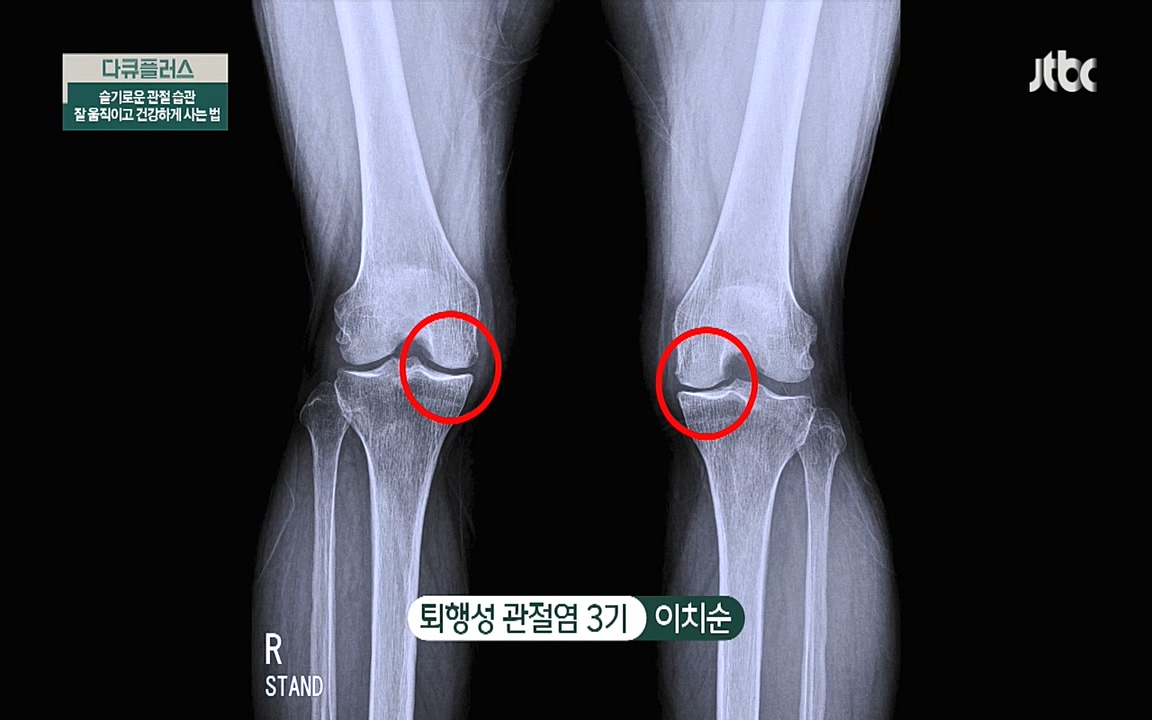

또한 병원에 가기 전날 질환증상과 며칠 동안 먹었던 약과 음식, ... 퇴행성 관절염은 노화와 반복된 관절 사용으로 관절을 보호하고 있는 연골조직이...